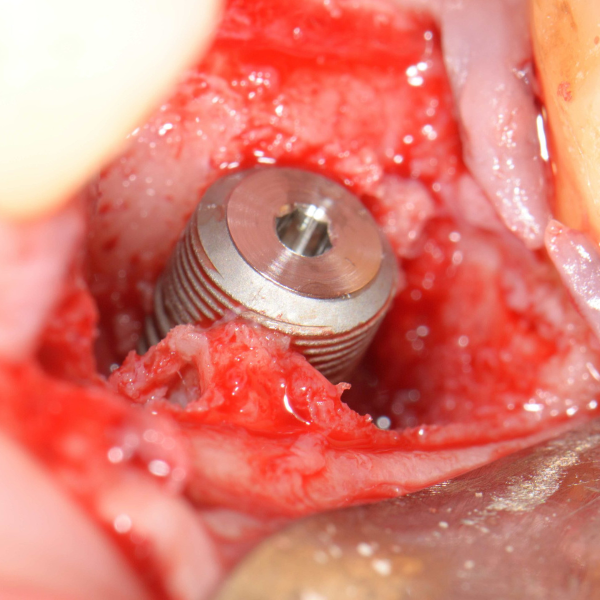

Tooth 14 slightly increased mobility, tenderness and bite pain. Suspected root fracture